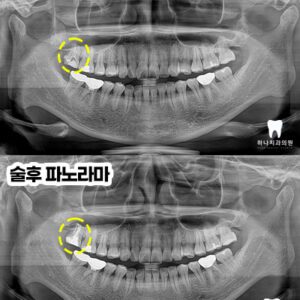

우선 CT 촬영 후 사진에서 보았을 때

원심 근관의 충전을 보면 중앙을

충전물이 지나지 않는 것을

확인할 수 있었습니다.

모든 근관은 치근의 중앙을 지난다는

원칙에 위배되어 하나의 근관이

더 있다는 결론을 도출할 수 있었는데요.

4회에 걸쳐진 치료를 완료하고

근관의 완전한 확보, 세척, 충전을

완료한 뒤 마무리 후 본뜨기 전의 모습입니다.

앞으로 2년 이상의 염증 부분의

잇몸뼈 리모델링 기간을 거쳐야

성공했음을 확신할 수 있다고

말씀드렸습니다.